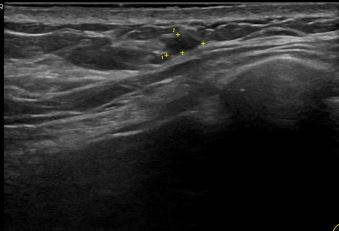

상기환자는 외부검사 이상소견으로 내원하신 60대 중반 여성분으로 의심스러운 좌측 혹 조직검사 시행해 유방암 진단되었습니다